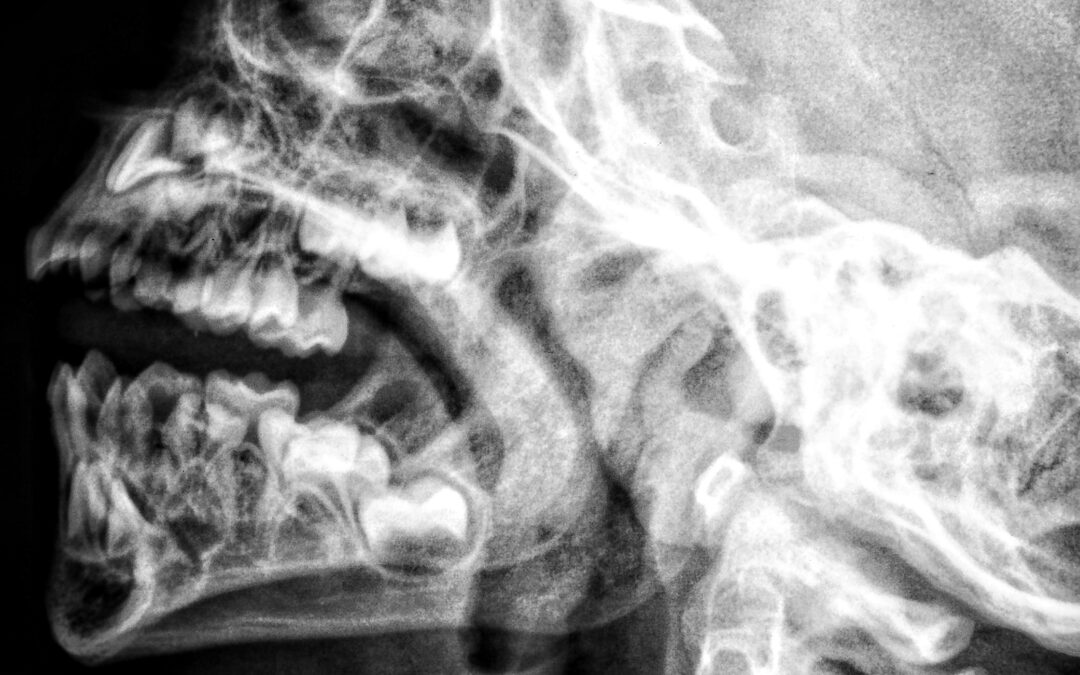

„Nu se vede clar pe radiografie… e ceva grav?” Nu ne grăbim spre concluzii. Ce este un dinte supranumerar? Un dinte în plus, frecvent între incisivi. Limitările radiografiei imagine 2D suprapuneri interpretare limitată Diagnosticul NU se pune pripit Medicina corectă...